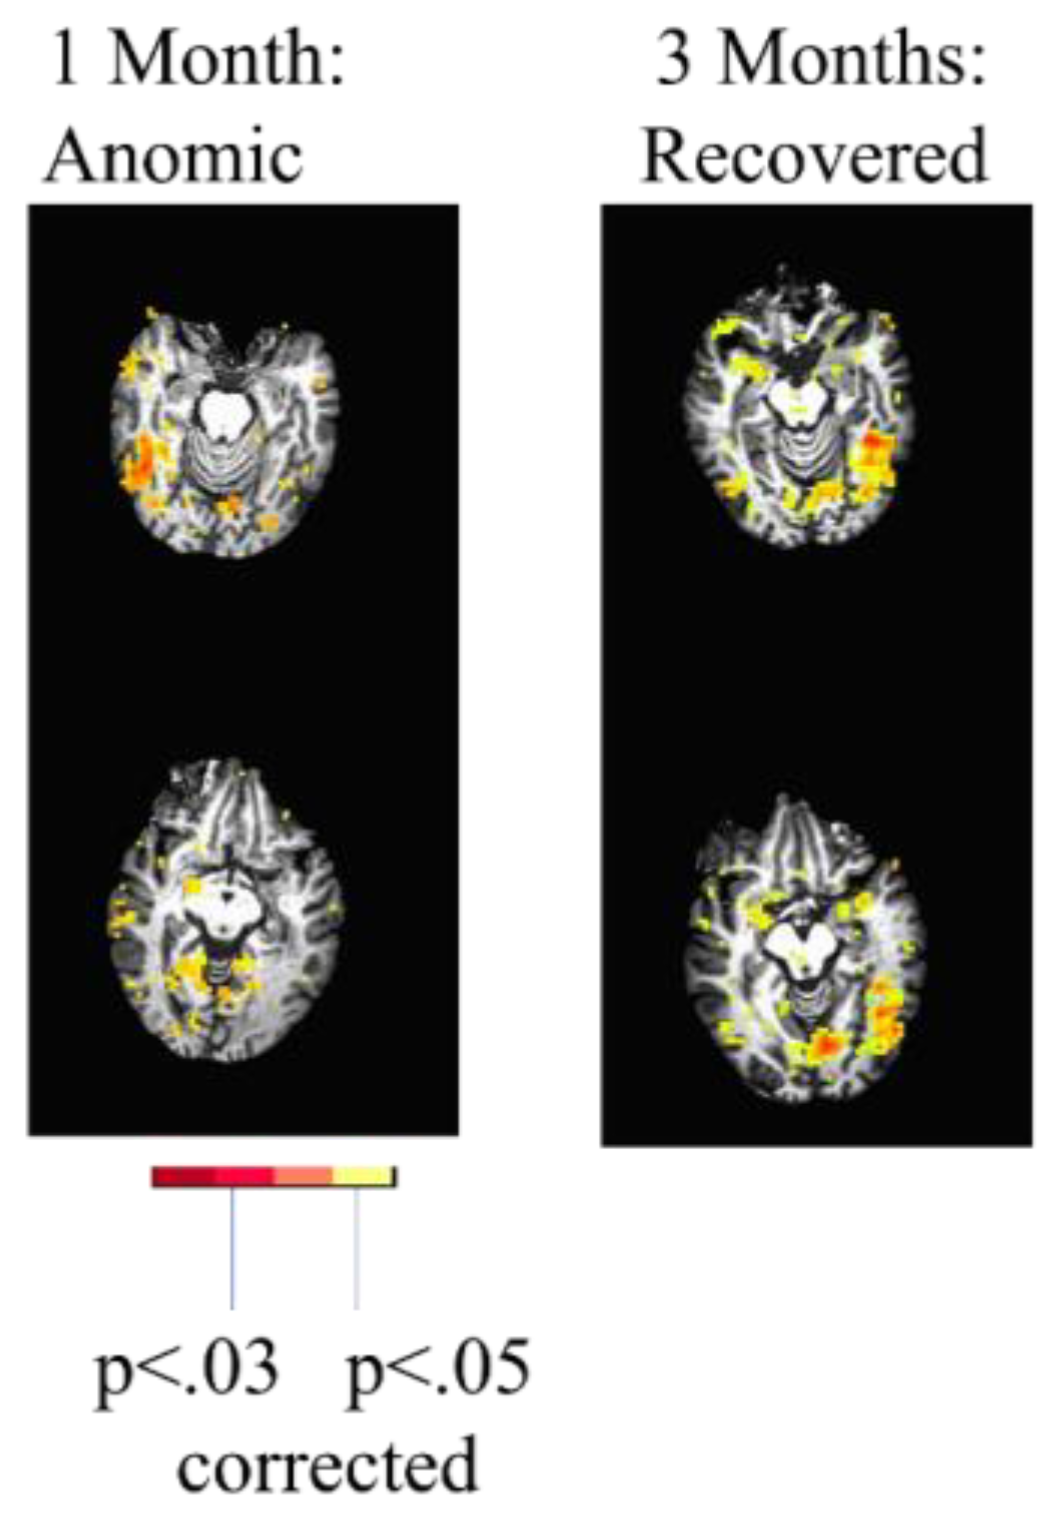

A later study of individuals with multimodal imaging acutely and at subsequent time points also demonstrated distinct mechanisms of recovery, including: (a) reperfusion; (b) recovery from diaschisis; (c) "reorganization", whereby undamaged regions show increased activation during recovery [27]. “Reorganization” may actually be a process of relying more heavily on previously present but “supportive” or underused networks (e.g., regions homologous to the left hemisphere language network) [28]. While a previous group study indicated that, on average, diaschisis occurs acutely in PSA [3], this case series found that acute diaschisis was far from universal [27]. One individual with PSA due to a left thalamic lesion showed clear evidence of recovery from diaschisis. This individual showed reduced activation in the left hemisphere language cortex but activation of the right hemisphere homologous network at one month post-stroke (subacutely) associated with picture naming (vs. saying “scrambled” in response to a scrambled picture), followed by re-activation of the left language network at 3 months post-stroke (Figure 1).

Figure 1. fMRI study of object naming showed minimal activation in the intact left temporal cortex at one month but activation of the homologous right temporal cortex, when he had slow but accurate naming (left). He showed normal activation of left temporal cortex at 3 months, when his naming had recovered in terms of latency (right).